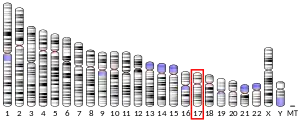

The gene is located near the Smith-Magenis syndrome region on chromosome 17.[5]